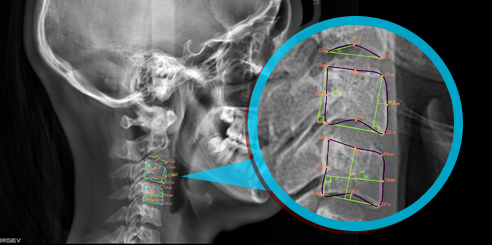

Finally, CEPH Measurement (Optional) in Dental CBCT (AI+CEPH)

The AI model analyzes large data sets to detect orthodontic landmarks and generate accurate cephalometric measurements and reports.

Therefore, orthodontists can assess and plan treatments with confidence.